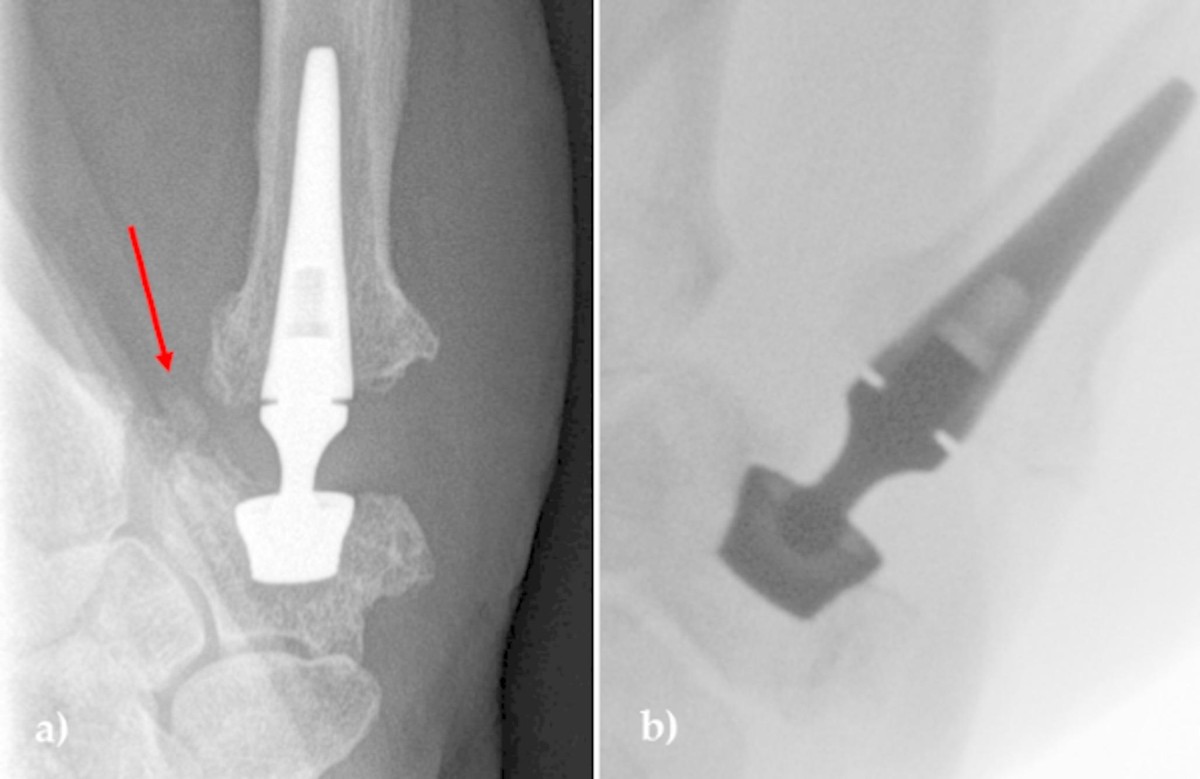

TOUCH® CMC 1 Prosthesis

• The TOUCH® CMC 1 prosthesis is a cementless, dual-mobility ball-and-socket total arthroplasty for the thumb carpometacarpal joint intended for adults with Eaton–Littler stage II–III osteoarthritis after failed nonoperative care

• Compared with trapeziectomy/LRTI, the design rationale is to preserve thumb length and pinch by replacing the diseased articulation and using a dual-mobility liner intended to reduce impingement and dislocation; available evidence is manufacturer-reported and long-term data are still accumulating

• trapezial cup made of stainless steel with titanium plasma-spray and hydroxyapatite coating, available in spherical and conical geometries

• modular neck in stainless steel with a cross-linked UHMWPE liner providing dual-mobility articulation

• ball-and-socket dual-mobility construct designed to permit opposition, abduction, and retropulsion while increasing jump distance to mitigate dislocation

• potential events include infection, hematoma, pain, tendon disorders including De Quervain and trigger thumb, stiffness, nerve irritation, complex regional pain syndrome, perioperative fractures, metallosis, osteolysis, heterotopic ossification, loosening or migration, dislocation, mechanical failure, and need for secondary surgery including revision or conversion

• manufacturer-reported data from the pivotal cohort noted nine secondary surgical interventions among 149 TOUCH implants within 24 months compared with one among 76 LRTI procedures; comparative interpretation is limited by propensity-score methodology and statistical concerns noted by regulators